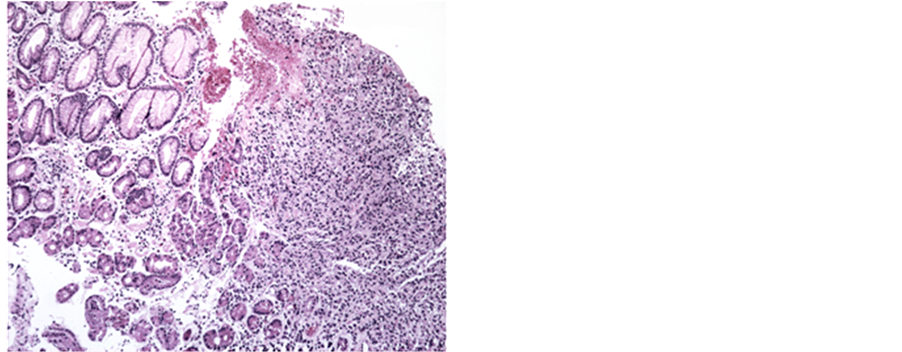

In May 2014, during the monitoring colonoscopy, disease in remission was seen in ileum and colon (Figure 1).

Figure 1. Colonic mucosa with moderate distortion of glandular architecture (glands with varying diameters, irregular spacing) because of fibrosis of the lamina propria and inflammation.